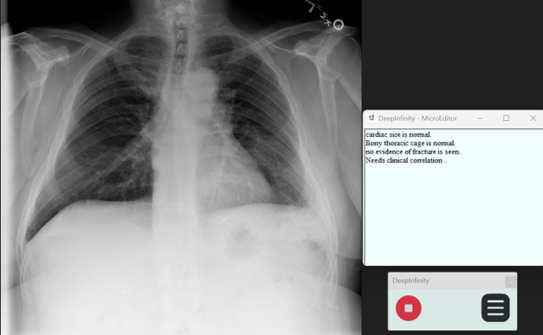

Step 15: Micro Editor for instant reporting

Click on the Menu button and click on Micro editor button to open micro editor

Sample Report Using Micro Editor